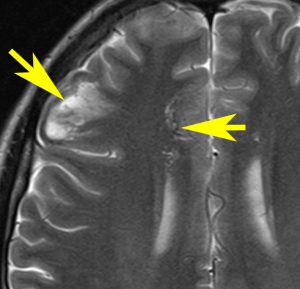

NF-2で脳腫瘍と間違っていはいけない大脳の病変

- NF-1よりずっと少ないのですが,NF-2でも大脳の病変はしばしばみられます

- MRIでグリオーマのようにみえますがそうではありません。T2強調画像で白く見えてガドリニウム造影されないのが一般的な特徴です

- 微小過誤腫 (microhamartoma)とか皮質異形成 (cortical dysplasia)とか血管周囲腔拡大 (Virchow-Robin space enlargement)とかいわれるものです

左側の病変はおそらく皮質異形成 cortical dysplasiaで,右中央寄りの病変はVirchow-Robin spaceの拡大です。